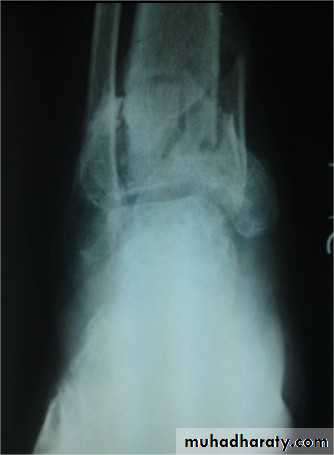

Comminuted fractures of the tibial plafond (Pilon fracture)

Severe axial compression of the ankle (FFH).

Shattering of ankle joint surface.

Swelling and blistering; treated by elevation and calcaneal traction.

Secondary Osteoarthritis is common.